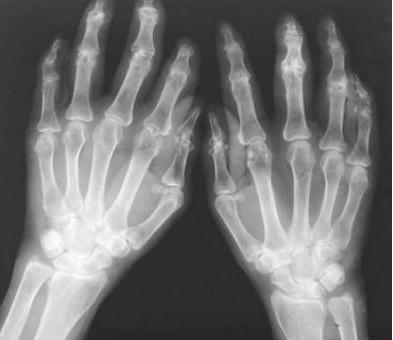

类风湿性关节炎发作时的疼痛,让人难以承受,苦不堪言,影响着患者的生活和工作。更重要的是类风湿性关节炎难治愈,而且很容复发,这往往使患者苦不堪言。那么类风湿性关节炎的病理表现有哪些呢?

1、滑膜:在急性关节炎的早期会导致滑膜增厚,充血和水肿,同时也会导致绒毛增生。在这一期间,血管翳(肉芽组织)开始从关节 软骨边缘逐渐覆盖关节软骨,并会腐蚀骨质,导致滑液增多、变得稀薄、混浊,到晚期会出现血管翳机化,形成厚的纤维组织,终也 就会导致关节纤维性强直。

2、关节软骨:关节会被多种酶(胶原酶,蛋白酶、弹性蛋白酶)腐蚀而变得粗糙、变薄,然后会导致局限性坏死。这种现象与骨关节 恰恰相反,这种疾病首先侵犯不负重的部分,然后并可继发增生性改变。